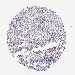

UROTHELIAL CANCER - Protein expressioni

A mouse-over function shows sample information and annotation data. Click on an image to view it in a full screen mode. Samples can be filtered based on level of antibody staining by selecting one or several of the following categories: high, medium, low and not detected. The assay and annotation is described here.

Note that samples used for immunohistochemistry by the Human Protein Atlas do not correspond to samples in the TCGA dataset.

Antibody stainingi

Antibody staining in the annotated cell types in the current human tissue is reported as not detected, low, medium, or high, based on conventional immunohistochemistry profiling in selected tissues. This score is based on the combination of the staining intensity and fraction of stained cells.

Each image is clickable and will lead to virtual microscopy that enables deeper exploration of all samples and also displays staining intensity scores, fraction scores and subcellular localization as well as patient and tissue information for each sample.

Antibody HPA046800

Staining

High

Medium

Low

Not detected

Intensity

Strong

Moderate

Weak

Negative

Quantity

>75%

75%-25%

<25%

None

Location

Nuclear

Cytoplasmic/membranous

Cytoplasmic/membranous,nuclear

Urothelial carcinoma, High grade

Urothelial carcinoma, Low grade